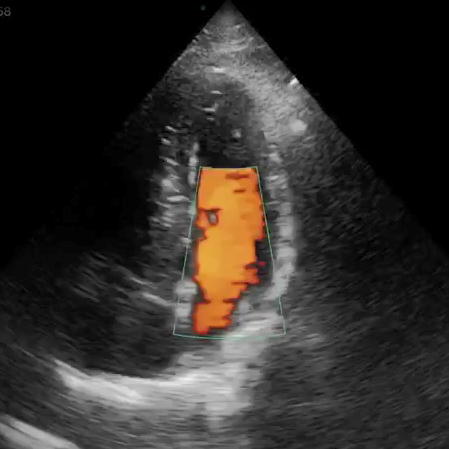

Modos de escaneo: B, B/M, Color, PW

Exámenes básicos y control de flujo cardíaco o vascular en entornos clínicos y extrahospitalarios.